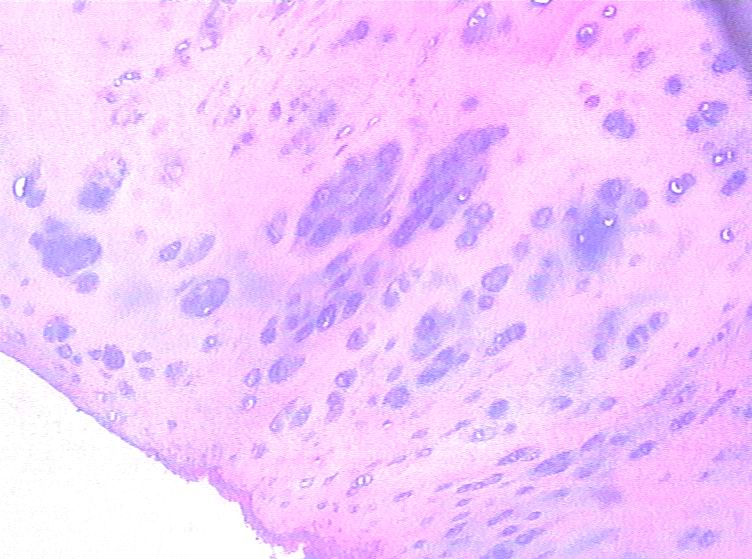

男,48岁,肿块直径1.5CM。

高疑软骨肉瘤,请同行会诊。

肿块位于何处,就楼主所给图片无分叶状结构,无粘液样基质,无双核软骨细胞无核异型,不符合软骨肉瘤,应该是个良性病变。

请传X线片及详细的临床资料。这些图像不足以诊断恶性。

不足诊断恶性